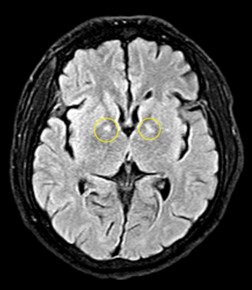

Hình ảnh tổn thương não của bệnh nhân nam

Bác sĩ điều trị, TS. Nguyễn Đăng Đức - Trung tâm Chống độc cho biết: Ba trường hợp trên đều đốt than củi để sưởi ấm trong phòng kín dẫn đến ngộ độc khí CO. Hiện các bệnh nhân đang được điều trị hồi sức tích cực, theo dõi, đánh giá các tổn thương và nguy cơ di chứng. Hiện bệnh nhân nam có tổn thương não. Các bệnh nhân nữ tổn thương tim, suy tim, tiêu cơ tim và nguy cơ di chứng với tâm thần, thần kinh rất cao.